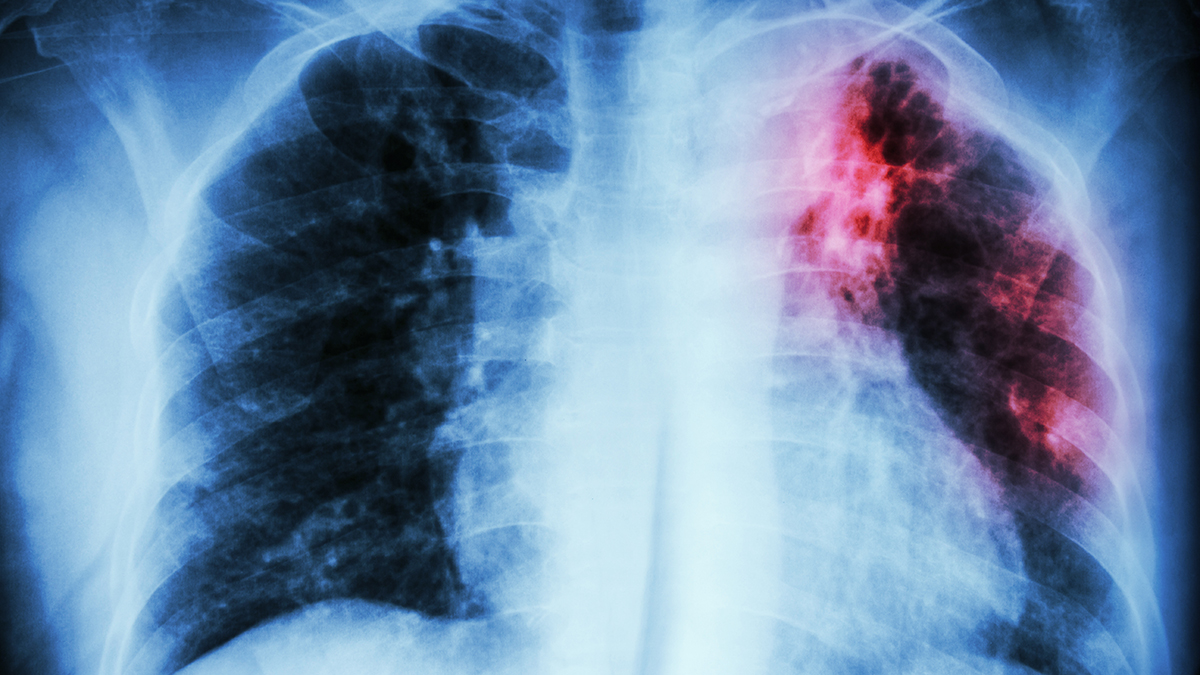

Возбудитель болезни распространяется воздушно-капельным путём: при кашле, разговоре или чихании частицы мокроты с микобактериями оседают на поверхностях в общественных местах. Они сохраняют активность до трёх месяцев, устойчивы к высоким температурам и большинству дезинфектантов. Иногда инфекция проникает в организм через посуду, гигиенические принадлежности или даже мясо заражённых животных.

Как отметила Боброва, главная сложность терапии — способность микроорганизмов быстро адаптироваться к антибиотикам. Даже комплексное лечение не всегда гарантирует полное выздоровление. Врач призвала не забывать о регулярной флюорографии, гигиене и осторожности в общественных пространствах.